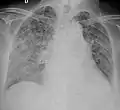

A case of miliary tuberculosis in an 82-year-old woman:

- X-ray, 13 days after onset, showing bilateral interstitial infiltrates